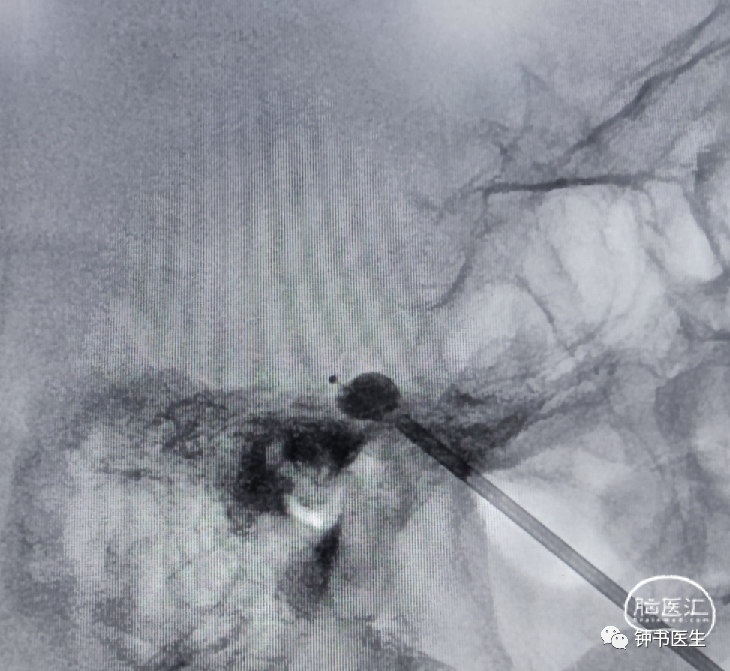

拟行右侧三叉神经球囊压迫治疗。

放入球囊导管 , 不超过斜坡线后5mm。

充盈球囊,压迫2分钟。手术结束!

皮穿刺半月神经节微球囊压迫术

(PBC)

该技术的创伤非常小,也称针尖内的手术,整个创口仅1个针眼大小,操作时间仅需约10-30分钟左右。而且对于高龄、不能耐受或不愿进行微血管减压术(开颅)的患者,微创治疗(球囊)是很好的治疗选择。